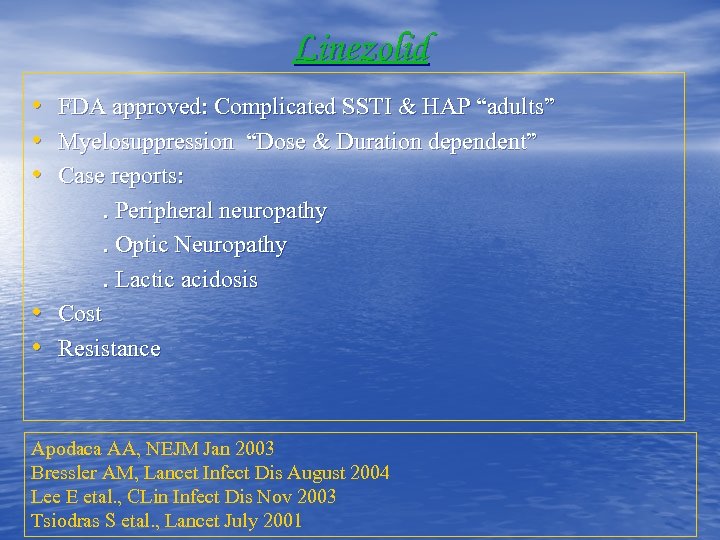

Linezolid • • • FDA approved: Complicated SSTI & HAP “adults” Myelosuppression “Dose & Duration dependent” Case reports: . Peripheral neuropathy. Optic Neuropathy. Lactic acidosis Cost Resistance Apodaca AA, NEJM Jan 2003 Bressler AM, Lancet Infect Dis August 2004 Lee E etal. , CLin Infect Dis Nov 2003 Tsiodras S etal. , Lancet July 2001

Linezolid • • • FDA approved: Complicated SSTI & HAP “adults” Myelosuppression “Dose & Duration dependent” Case reports: . Peripheral neuropathy. Optic Neuropathy. Lactic acidosis Cost Resistance Apodaca AA, NEJM Jan 2003 Bressler AM, Lancet Infect Dis August 2004 Lee E etal. , CLin Infect Dis Nov 2003 Tsiodras S etal. , Lancet July 2001